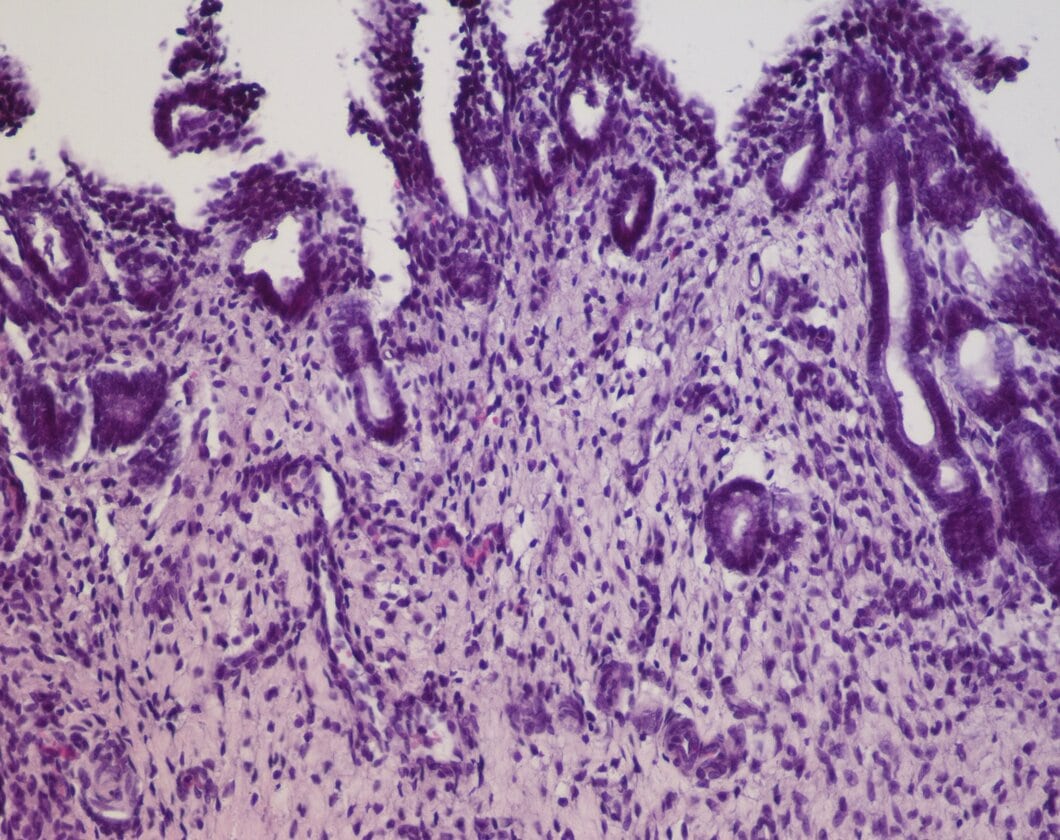

(A). Endometrio con edema e infiltrado mononuclear compuesto principalmente por macrófagos. H&E, Barra = 100µm.

La masa pedunculada estaba compuesta por tejido conectivo muy vascularizado, con fibroblastos, fibrocitos y macrófagos, y tapizada por células epiteliales normales (Figura 3A-B). La masa nodular estaba compuesta por abundante cantidad de células fusiformes, dispuestas en bandas entrelazadas, con un núcleo único, grande, central, redondo u oval con un patrón de cromatina en grumos y moderada cantidad de citoplasma. No se observaron figuras mitóticas (Figura 4A-B). Mediante la coloración especial de van Gieson se confirmó la presencia de abundantes fibras de musculo liso y escaso tejido conjuntivo (Figura 4C). Se formuló el diagnóstico de pólipo y leiomioma uterinos. Se otorgó el alta médico y quirúrgico a los 10 días de la intervención. La paciente se recuperó totalmente. Doce meses post-intervención la misma concurrió a consulta para realizar un control anual en el cual se no se evidenciaron signos clínicos de la enfermedad.